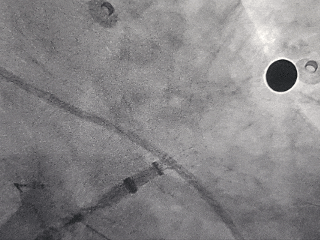

房间隔穿刺

射频消融前穿刺双孔

射频消融

DSA造影复测缺损

右肩位:RAO 30° +CRAN 20°

肝位:RAO 30° +CAU 20°